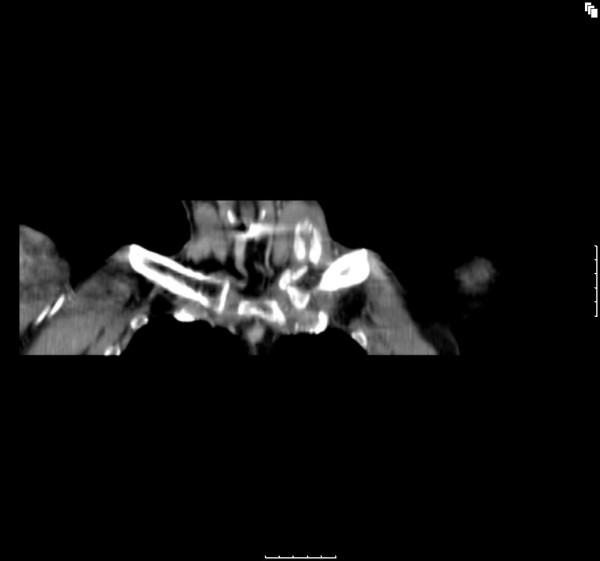

Despite it close proximity to the sternocleidomastoid muscle and myositis ossificans recognised as a known complication of any fracture, the two have never previously been described in association secondary to a fracture of the clavicle. We present a case where myositis ossificans affecting the sternocleiodomastoid was detected in the post-injury phase of a clavicle fracture.

尽管锁骨骨折紧邻胸锁乳突肌,且骨化性肌炎被认为是任何骨折的已知并发症,但此前从未有过二者继发于锁骨骨折相关联的描述。我们报告一例在锁骨骨折伤后阶段检测到胸锁乳突肌发生骨化性肌炎的病例。

该病例表明,锁骨内侧三分之一骨折后,胸锁乳突肌可发生局限性创伤性骨化性肌炎。